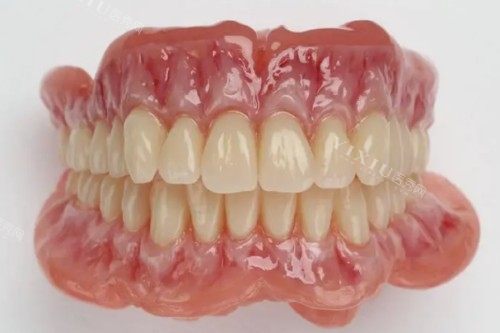

全口吸附性义齿是一种覆盖整个牙弓的修复体,适用于上颌或下颌牙齿全部缺失的情况。它利用口腔黏膜与义齿基托之间的吸附力,使义齿能够稳固地固定在口腔内。与传统义齿相比,吸附性义齿在舒适度和稳定性方面有所提升。

美观自然:牙齿排列和颜色接近天然牙。